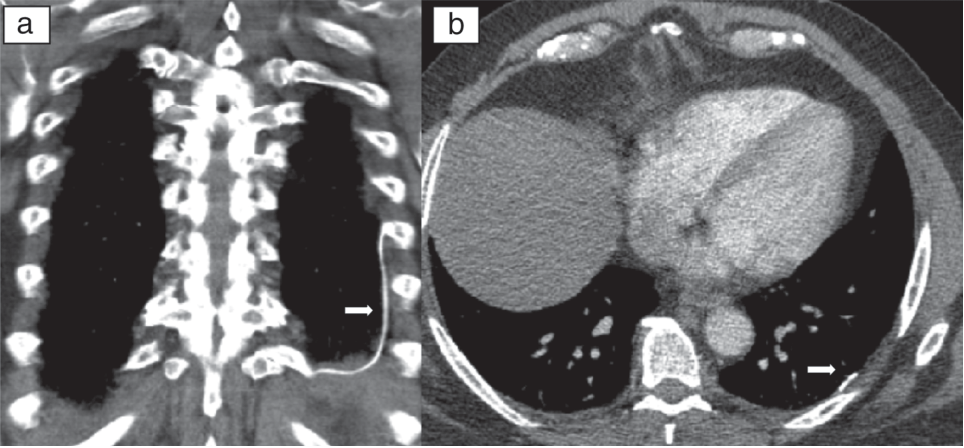

Magnetresonanz-Bildgebung (MRI)

Computerisierte Axialtomographie (CAT) -Scan